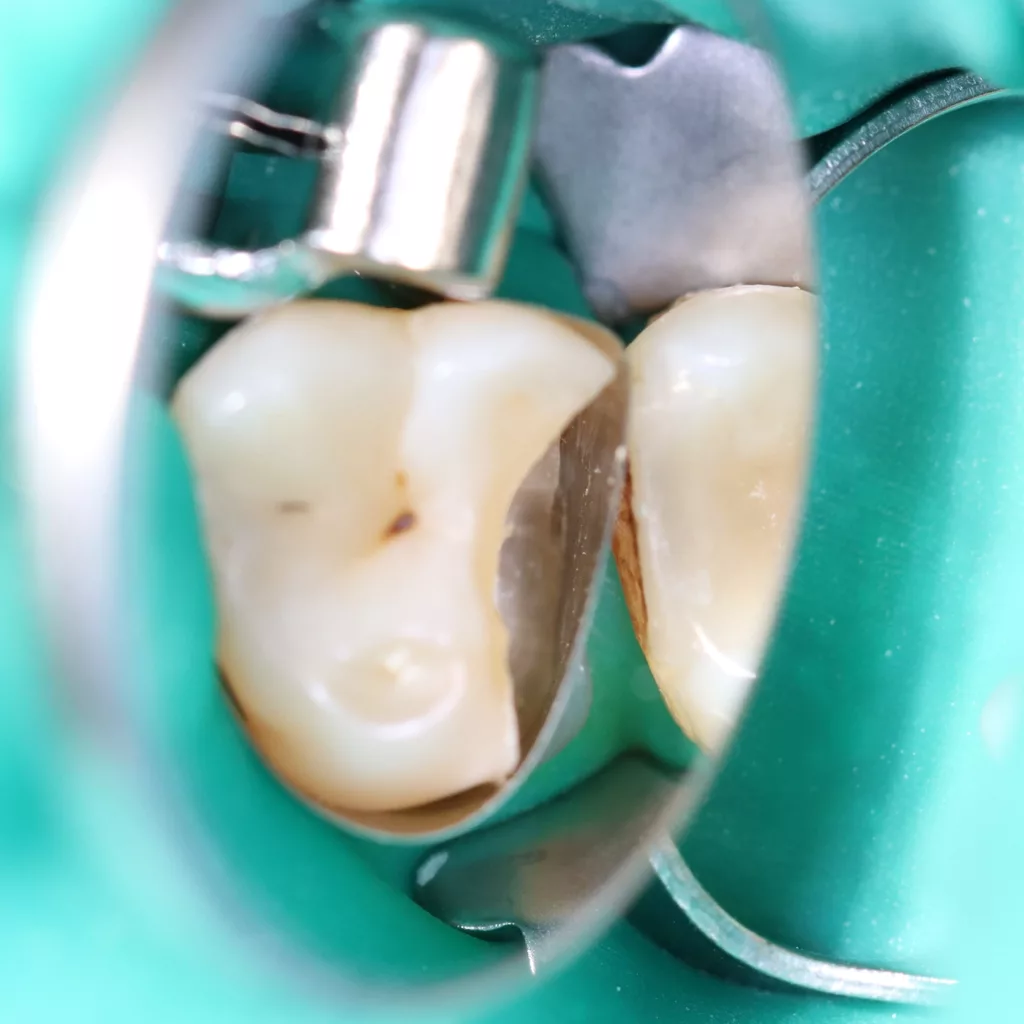

Wird eine profunde kariöse Läsion behandelt, empfiehlt sich folgendes Vorgehen [5]: Zunächst sollte in einem ersten Schritt ein Kofferdam appliziert werden, um eine möglichst keimfreie Arbeitsweise zu gewährleisten. Nach Präparation einer Zugangskavität, wenn dies notwendig ist, erfolgt die Kariesexkavation mittels Rosenbohrern oder Handexkavatoren. Wird in pulpanahen Arealen eine Eröffnung der Pulpa erwartet, sollte das Instrument gewechselt und ein sauberer Rosenbohrer genutzt werden. Tritt nach vollständiger Kariesexkavation keine Eröffnung der Pulpa ein, ist aber von einer dünnen Restdentindicke von etwa 300 µm auszugehen, oftmals erkenntlich durch eine zartrosa hindurchschimmernde Pulpa, sollte nach Kavitätentoilette mittels Natriumhypochlorit (NaOCl) 3% eine indirekte Überkappung mit einem hydraulischen Kalziumsilikatzement erfolgen [5]. NaOCl dient dazu, Bakterien und Toxine zu neutralisieren und das Dentin zu desinfizieren. Die Unterfüllung aus Kalziumsilikatzement soll auch desinfizierend wirken, das Pulpagewebe zur Heilung anregen und vor möglicherweise durch das Dentin penetrierenden Monomeren aus dem Dentinadhäsivsystem schützen [5], da diese die regelrechte Funktion der Odontoblasten beeinträchtigen können [9,40]. Im Anschluss muss eine direkte, dentinadhäsive Restauration zur Versorgung der Kavität platziert werden [5]. Die Abbildungen 1 bis 14 illustrieren das Vorgehen bei der Behandlung einer profunden kariösen Läsion mit indirekter Überkappung der Pulpa.